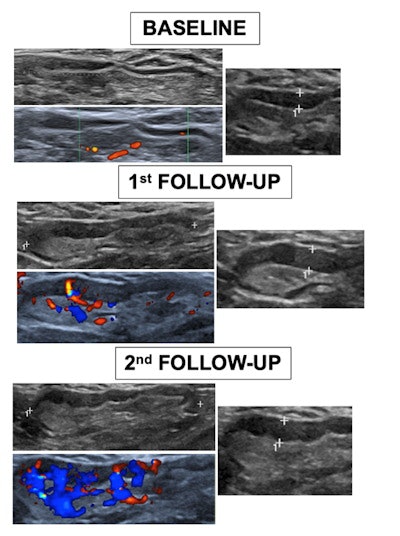

Three axillary ultrasound evaluations of the ipsilateral vaccinated arm were performed. They were done before vaccination (baseline), the week after the first dose, and the week after the second dose.

Comparative ultrasound images from one volunteer between baseline and the first and second follow-ups shows a significant gradual increment of maximum diameter, cortex, Bedi’s classification, and Doppler scale degree. Image courtesy of Dr. Alba Cristina Igual‐Rouilleault and European Radiology.The team recorded the following characteristics: the total number of visible nodes, the maximum measurements of the diameter and cortex, Bedi's classification, and color Doppler evaluation.